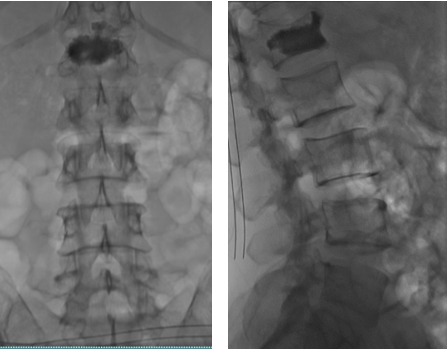

Chiều18/11, bệnh nhân đã được các bác sĩ  tại đơn nguyên Tim mạch can thiệp (DSA) và Khoa Ngoại CTCH tiến hành thủ thuật đổ xi măng cột sống số hóa xóa nền (DSA). Ngay ngày hôm sau, bệnh nhân đã đứng thẳng, đi lại bình thường.

Hình ảnh bơm xi măng vào thân đốt sống L1